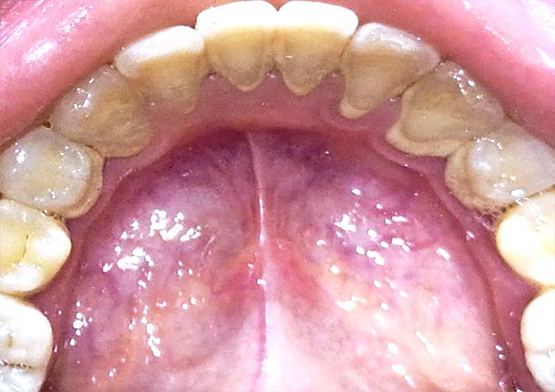

Hasil Scaling di Poli Gigi Alkindi

Before Scalling

After Scalling